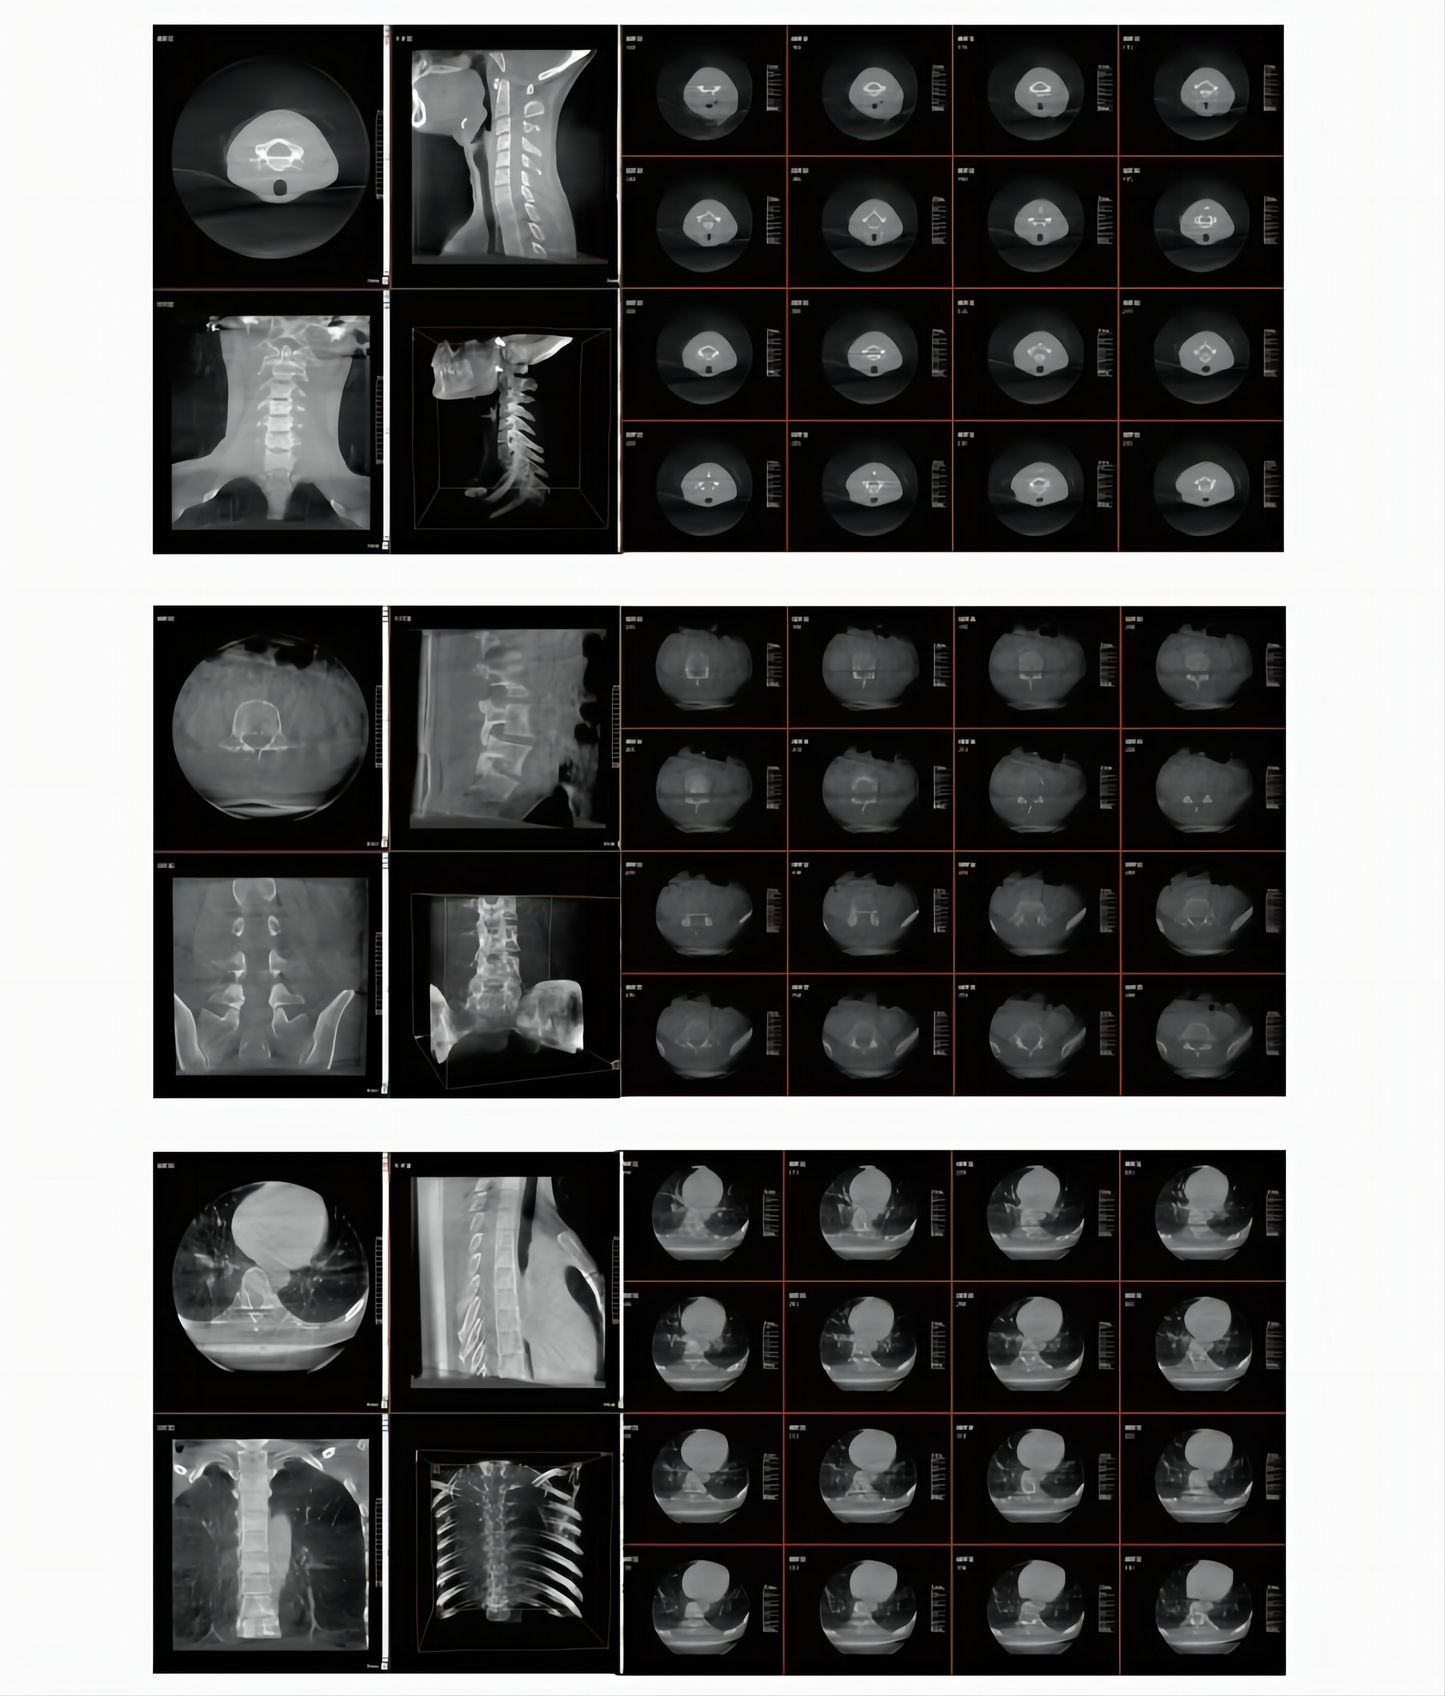

3. Intraoperative 3D Imaging

Intraoperative 3D imaging technology can generate 3D images in the coronal, sagittal and transverse planes of the corresponding parts during surgery. For example, in spinesurgery, the position of the implants relative to the vertebral foramen and the pedicle can be checked intraoperatively through 3D images to help doctors evaluate the effect of implant placement. Intraoperative examination optimizes the surgical process by replacing the traditional postoperative CT examination with intraoperative 3D imaging, which to a certain extent avoids revision surgeries, reduces the cost of surgery and shortens the hospital stay.

4. Larger 3D Imaging Area

The intraoperative 3D imaging area is up to 18cm3. Each dimension is 400 stereo pixels so the image quality is fine and clear. A larger intraoperative 3D FOV can help capture more image information (whole cervical spine, whole lumbar spine, seven thoracic spine segments, bilateral articulatio sacroiliaca, caput femoris and unilateral pelvis) in one shot.